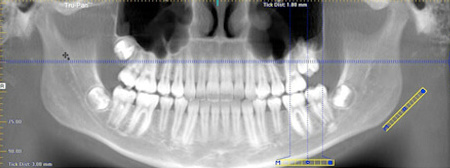

First, he took a CT scan of my entire head. Then he created a 3D digital image that allowed him to zoom in on the location of the implant and precisely measure the angle and depth needed for a solid plug.

When he showed me this photo, he was happy to point out that “Westerners” typically have denser bones than Japanese. He was sure this would make the implant more stable.

OK, it wasn’t that bad. Obviously, I could move my legs and arms. But there was no pain. After an hour, it was over. We went to do another CAT scan to confirm the angle was correct. Then he showed it to me as “before” and “after” images on a huge computer screen hung on the wall.